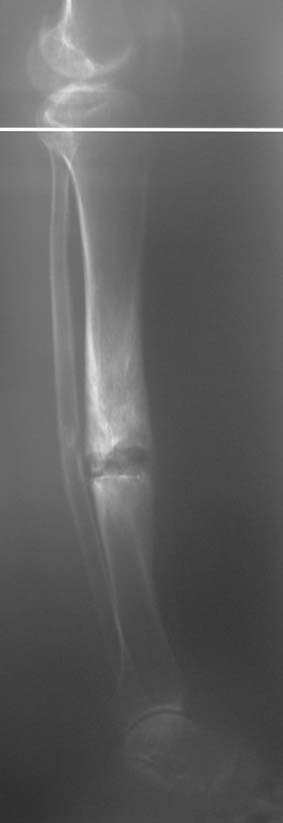

Chronic osteomyelitis leads to necrosis of bone and soft tissues. Dead bone is a nidus which hosts pathogenous microorganisms. Defence mechanisms of the host is usually not in optimum condition to deal with microorganisms. Antibiotics can’t reach the infection site because blood flow is disrupted. For these reasons, dead bone has to be completely removed by radical debridement.

Appropriate radical debridement necessitates excision of all necrotic bone and soft tissues, and frequently causes instability at the involved extremity. The remaining bone and soft tissue defect has to be fixed and reconstructed. The distraction osteogenesis method of Ilizarov is used successfully for achievement of union, correction of the deformity, elimination of limb length inequality and reconstruction of segmental bone defects.